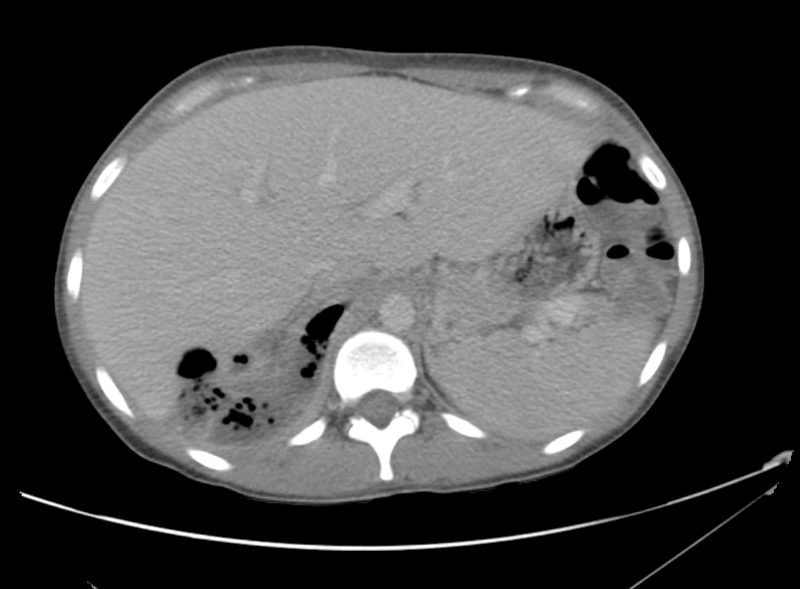

From radiologycases.my

Emphysematous pyelonephritis Radiology Cases Pyelo Nephr Itis management of pyelonephritis in adults. Learn about symptoms and treatment here. Pyelonephritis is generally a complication of an. A kidney infection (pyelonephritis) can be unpleasant, but it will usually improve if treated promptly. A urinary tract infection is described by location: If not treated properly, an infection can cause lasting damage to the kidneys. acute pyelonephritis is a. Pyelo Nephr Itis.